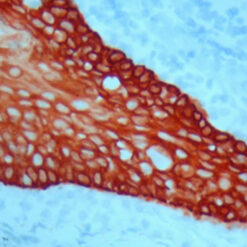

The Warthin-Starry Stain Kit is intended for use in the visualization of Spirochetes, Helicobacter pylori, Legionella pneumophila, and Cat Scratch Fever bacteria. This kit may be used on formalin-fixed, paraffin-embedded sections.